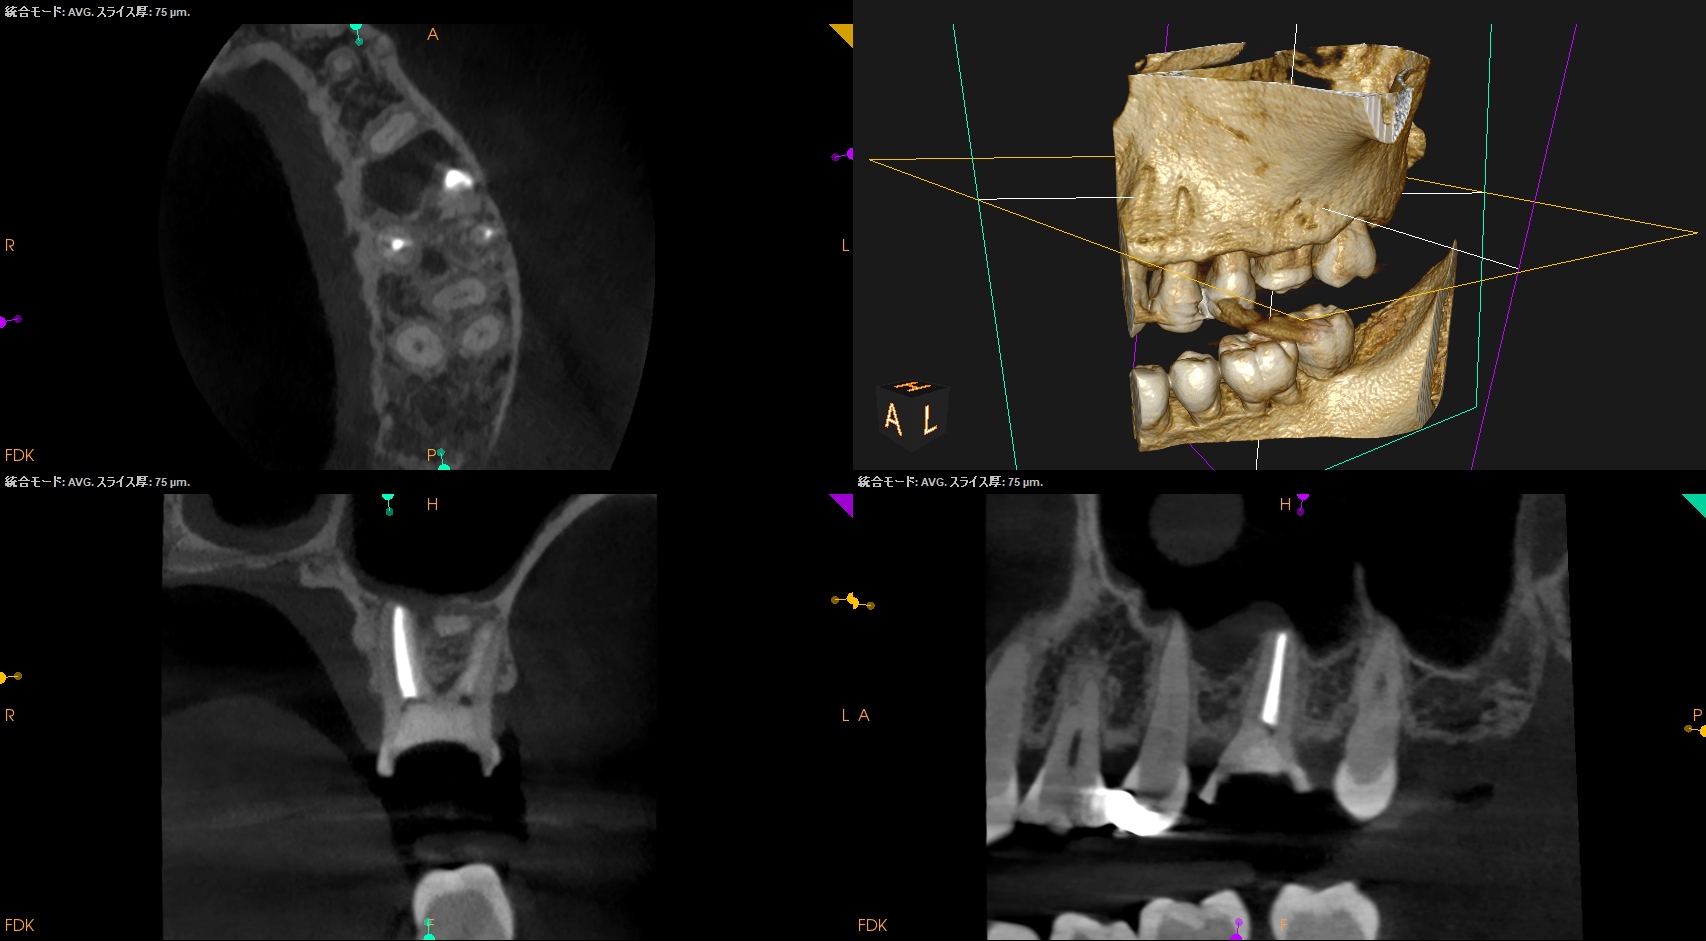

CBCT(2025.4.15)

MB

MBの根管口部あたりに穿孔が疑われる所見がある。

ストリッピングパーフォレーションというやつだ。

根充後に根管をBC Puttyで埋める必要があるだろう。

DB

P

DB,Pには何もない。

SelectiveにMBのみを扱う治療になるだろう。